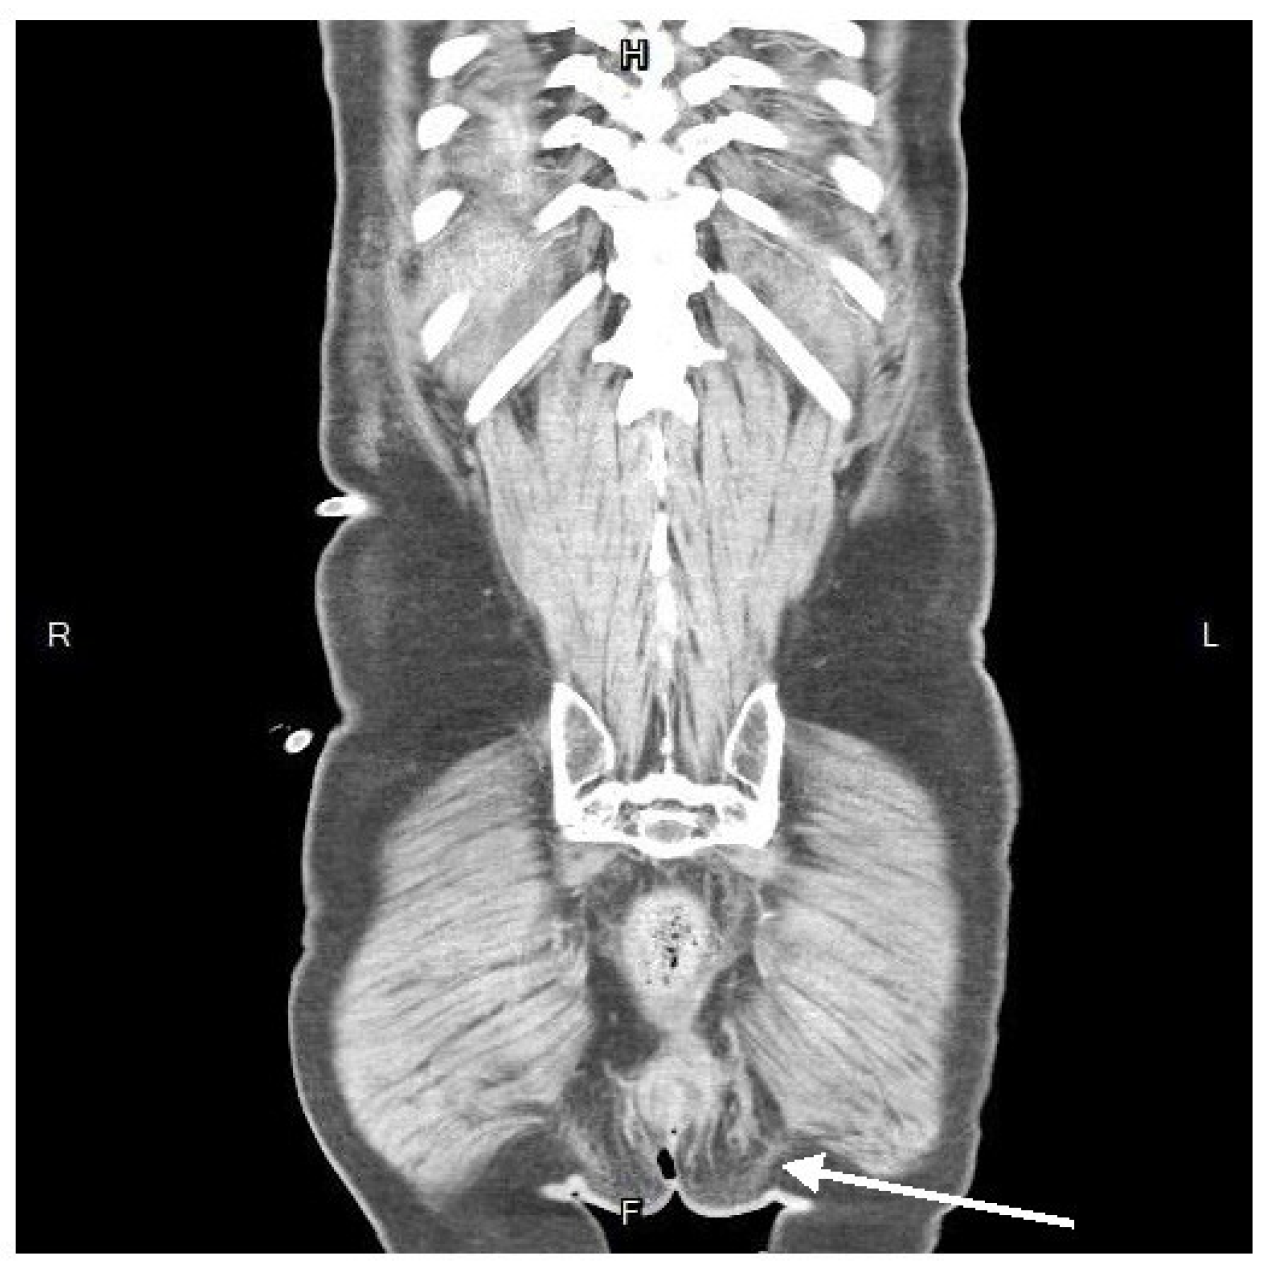

Physical examination revealed pain with deep palpation over the groin and suprapubic area, without rebounding tenderness or signs of deep vein thrombosis in the extremities. The digital rectal examination yielded negative of bloody discharge but noted mild nonspecific pain. The pain did not impact ambulation and normal gait and the strength testing was impaired. The patient did not report dysuria or increased urinary frequency. A plain abdominal radiograph was normal, and laboratory findings consisted of elevated white blood cell count and C-reactive protein (white blood cells, 27,830/μL; neutrophils, 90.6%; C-reactive protein, 21.65 mg/L). Abdominal contrast-enhanced computed tomography (CT) showed a heterogenous fluid-filled perianal abscess, 5.0x4.4x6.8 cm, (Figure 1) in the left perianal region, with extraperitoneal air spreading through the abdominal wall fascia. (Figure 2 and Figure 3)

Figure 2. Axial view in contrast-enhanced computed tomography. An emphysematous collection of spotted air at the perivesical space(arrow), dominantly on the left side.